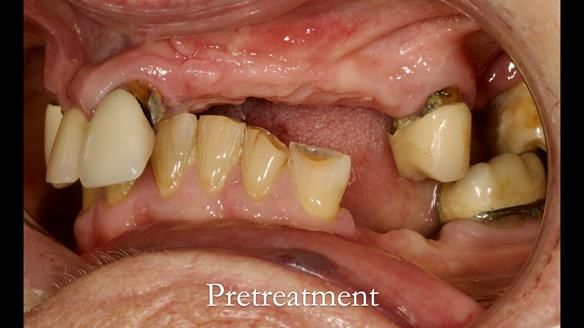

Aesthetically and functionally poor RPDs were replaced for Eileen, a 74 year old woman.

Referred to me by her general dental practitioner specifically for replacement RPDs.

Diagnoses

- Missing teeth in the upper and lower jaws

- Upper and lower metal based RPDs, poorly fitting, worn occlusal surface, reverse curve aesthetics, lacking support

- Poor dental appearance with reverse incisal curve

- The upper right central and lateral incisors with post crowns. Healthy and functionally secure but with poor appearance, contributing to the reverse curve.

- Moderate to heavily restored dentition with deep overbite (Class 2 div II)

- Yellowish lower front teeth with small amount of wear.

- The lower right canine (LR3) is worn with MOD cavity.